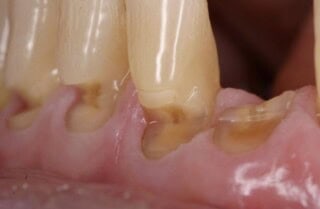

Art and the human body - its great to see other artists create such good art with details such as the facial structures! These lips, seen in Edinburgh, were so cleverly made! All our dentists are actualy artists - creating everyday artwork when replacing fillings, crowns, bonding…